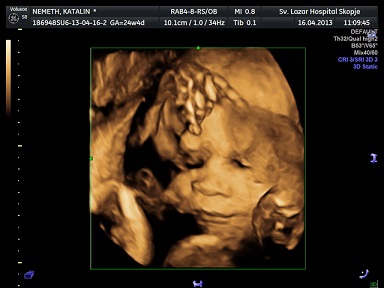

Nálunk 2 ezer forint különbség van a sima és a 4D között, de azt nem tudom, hogy akkor hogyan épül fel a vizsgálat, vagyis hogy miben más. Nekünk múltkor is felajánlotta, h cd-re veszi az egészet.... nem akartuk, de most nagyon akarjuk!!! majd jövök is mutizni

23. hét